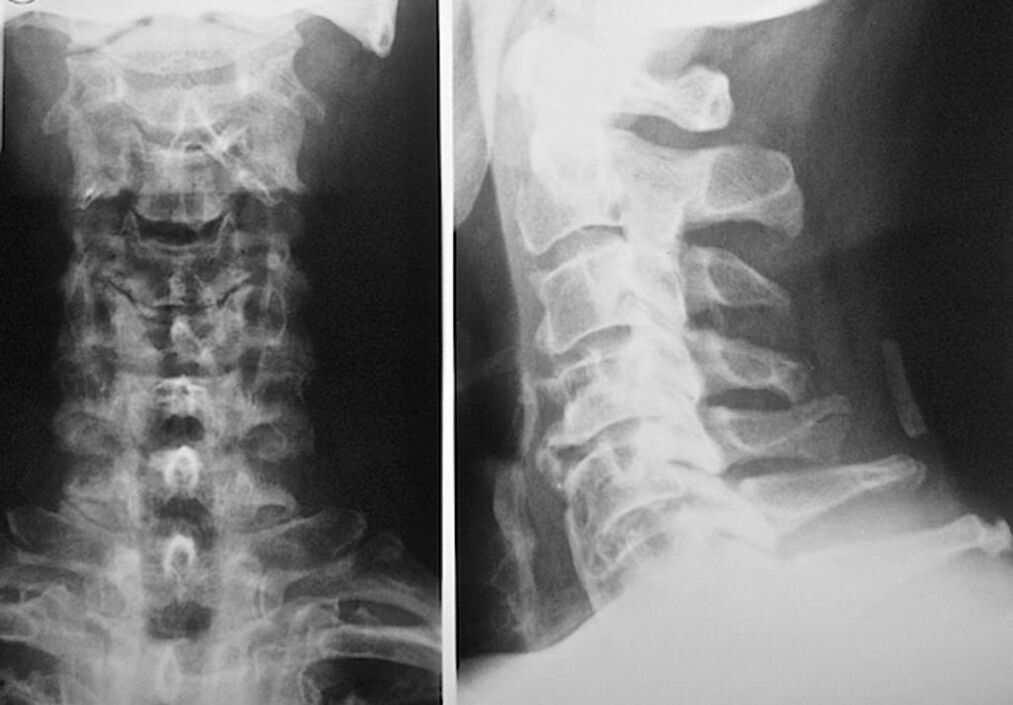

For the diagnosis and accurate assessment of the condition of the intervertebral discs, the following research methods are used:

- Radiography.

- CT scan.

- Magnetic tomography.

- Ultrasound scanning of neck vessels.

Each of them is completely safe for health and does not carry any threat of excessive exposure. Diagnosis of osteochondrosis of the cervical vertebrae, the treatment of which will be carried out throughout the rest of life, can be carried out after a simple visual examination. Any orthopedist can easily do this. An exception is the first stage of the disease, when there are no visible pathologies of the cervical region.